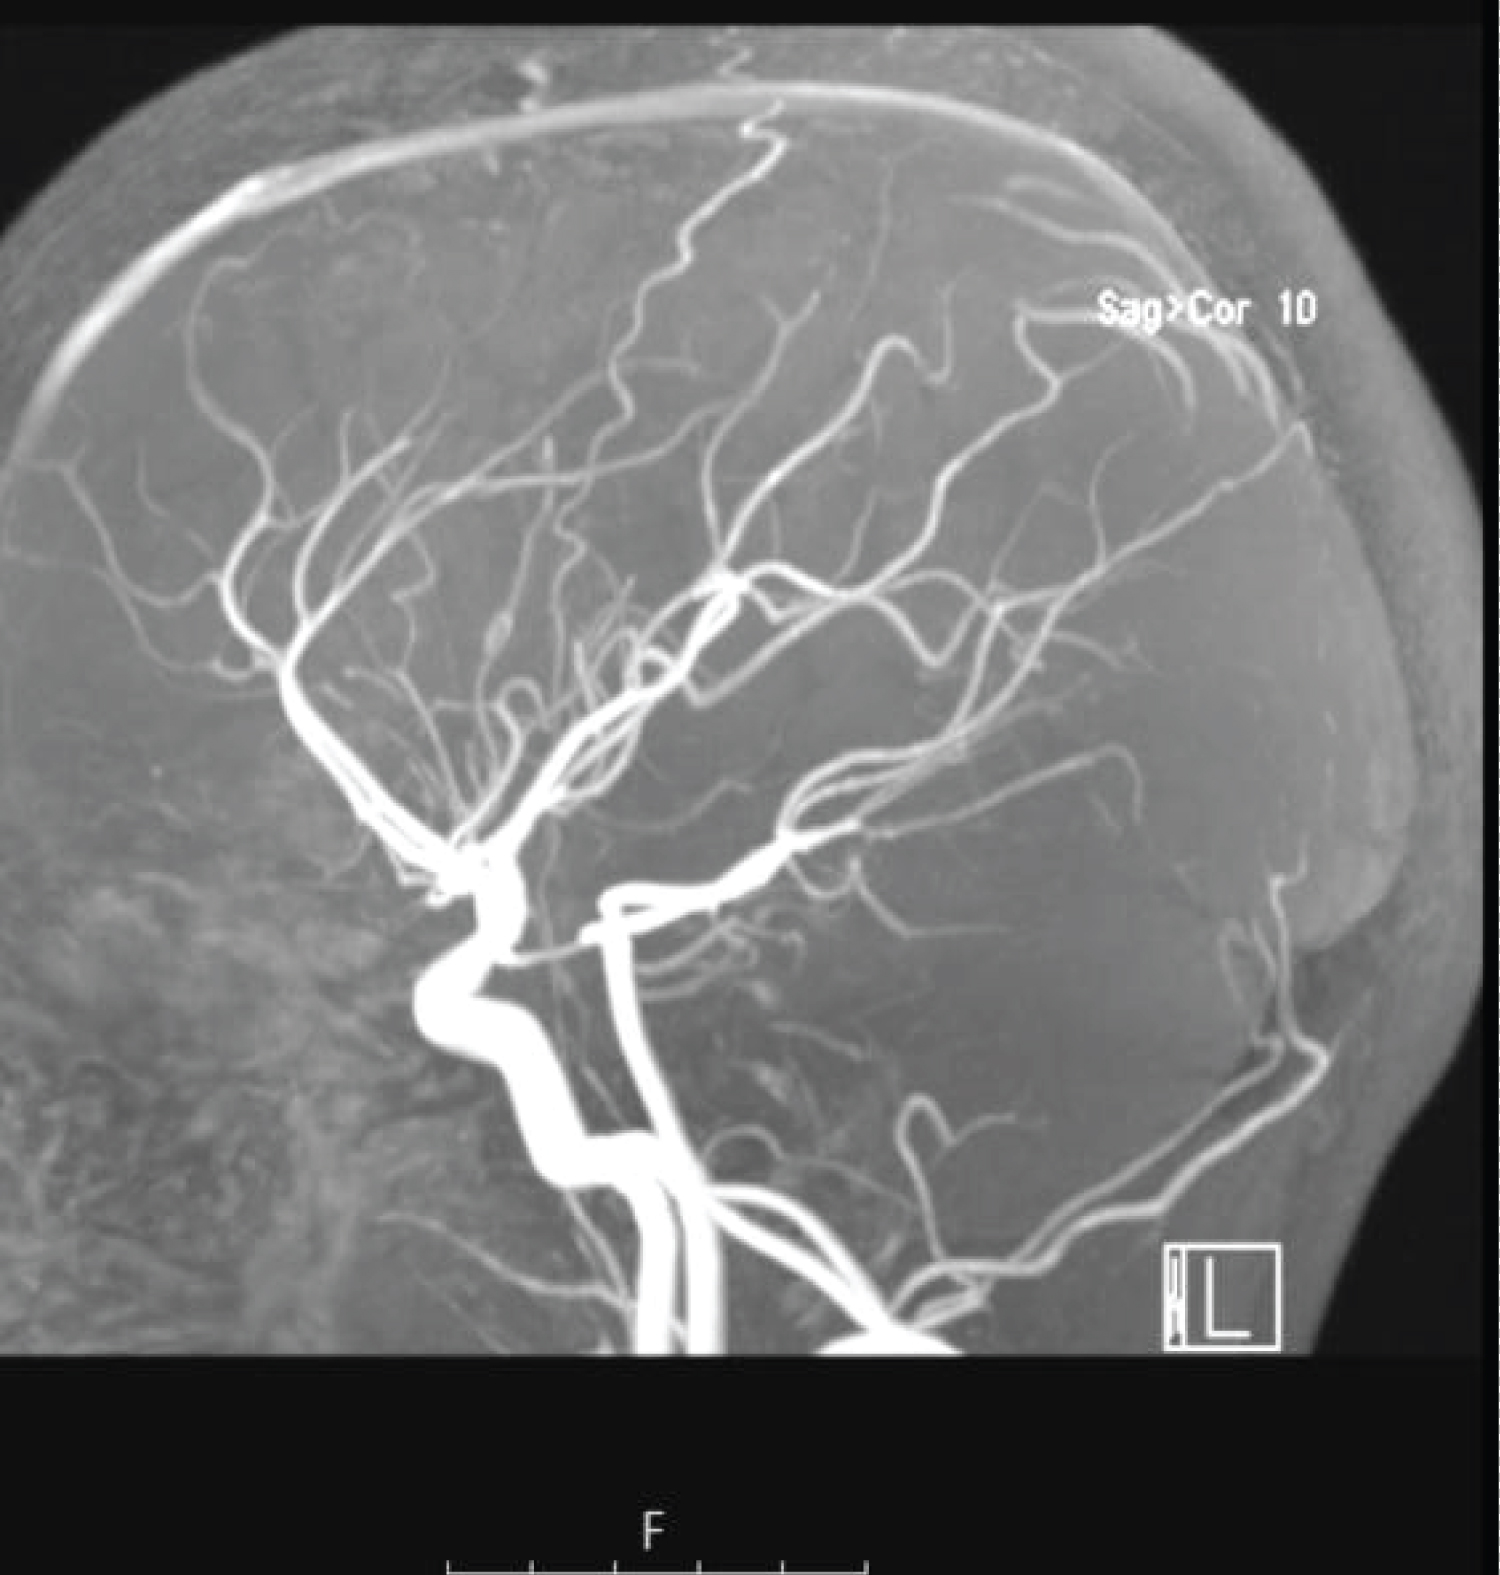

Surgical resection of the AVM (Spetzler-Martin grade II) was performed without major immediate complications but there was a slight deterioration of previous neurological deficits with right arm paresis. Postoperative cerebral angiography revealed no residual AVM (Figure 3). The rehabilitation program was maintained. He gradually recovered motor abilities and regained normal language function. The control magnetic resonance angiography showed no arteriovenous malformations (Figure 4). He remained clinically asymptomatic and without seizures, suspending valproate after 18 months.

Figure 3: Postoperative. (A) Lateral; (B) Anteroposterior cerebral angiograms of the left internal carotid artery revealing no residual AVM. View Figure 3

Figure 4: Control magnetic resonance angiography showed no arteriovenous malformations. View Figure 4